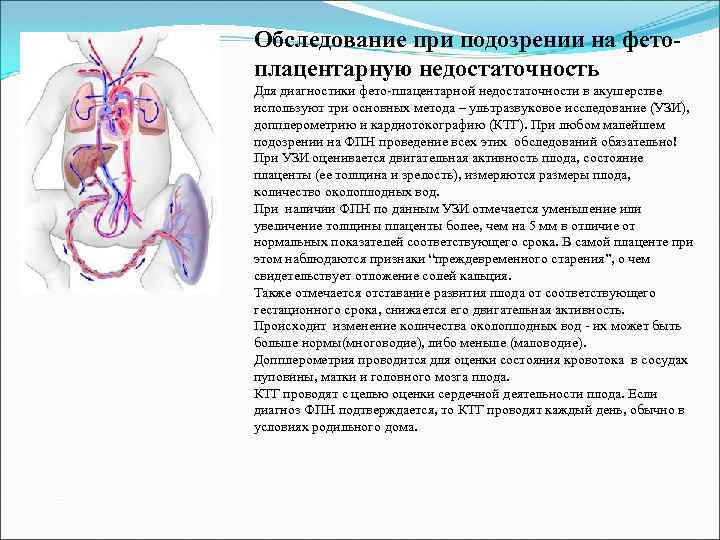

Обследование при подозрении на фетоплацентарную недостаточность Для диагностики фето-плацентарной недостаточности в акушерстве используют три основных метода – ультразвуковое исследование (УЗИ), допплерометрию и кардиотокографию (КТГ). При любом малейшем подозрении на ФПН проведение всех этих обследований обязательно! При УЗИ оценивается двигательная активность плода, состояние плаценты (ее толщина и зрелость), измеряются размеры плода, количество околоплодных вод. При наличии ФПН по данным УЗИ отмечается уменьшение или увеличение толщины плаценты более, чем на 5 мм в отличие от нормальных показателей соответствующего срока. В самой плаценте при этом наблюдаются признаки “преждевременного старения”, о чем свидетельствует отложение солей кальция. Также отмечается отставание развития плода от соответствующего гестационного срока, снижается его двигательная активность. Происходит изменение количества околоплодных вод - их может быть больше нормы(многоводие), либо меньше (маловодие). Допплерометрия проводится для оценки состояния кровотока в сосудах пуповины, матки и головного мозга плода. КТГ проводят с целью оценки сердечной деятельности плода. Если диагноз ФПН подтверждается, то КТГ проводят каждый день, обычно в условиях родильного дома.

Обследование при подозрении на фетоплацентарную недостаточность Для диагностики фето-плацентарной недостаточности в акушерстве используют три основных метода – ультразвуковое исследование (УЗИ), допплерометрию и кардиотокографию (КТГ). При любом малейшем подозрении на ФПН проведение всех этих обследований обязательно! При УЗИ оценивается двигательная активность плода, состояние плаценты (ее толщина и зрелость), измеряются размеры плода, количество околоплодных вод. При наличии ФПН по данным УЗИ отмечается уменьшение или увеличение толщины плаценты более, чем на 5 мм в отличие от нормальных показателей соответствующего срока. В самой плаценте при этом наблюдаются признаки “преждевременного старения”, о чем свидетельствует отложение солей кальция. Также отмечается отставание развития плода от соответствующего гестационного срока, снижается его двигательная активность. Происходит изменение количества околоплодных вод - их может быть больше нормы(многоводие), либо меньше (маловодие). Допплерометрия проводится для оценки состояния кровотока в сосудах пуповины, матки и головного мозга плода. КТГ проводят с целью оценки сердечной деятельности плода. Если диагноз ФПН подтверждается, то КТГ проводят каждый день, обычно в условиях родильного дома.